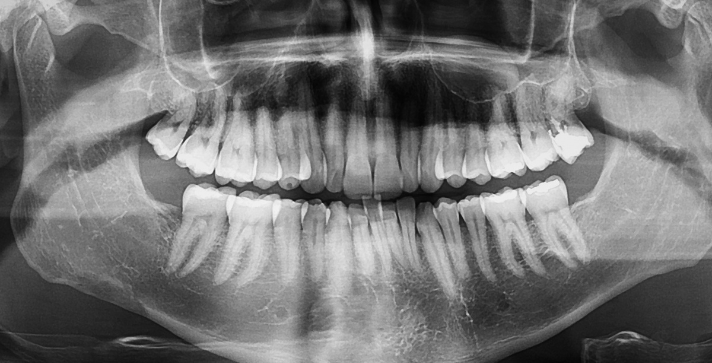

In the heart of Silicon Valley, dental care is defined by a fusion of precision, health, and cutting-edge technology. At Manassra Dental, Digital Dental X-rays (radiographs) serve as our diagnostic backbone, providing a high-tech, low-radiation window into what is happening beneath the surface of your smile.

What Can Digital X-Rays Reveal?

X-rays are the only definitive way to detect “hidden” issues that a visual exam might miss. At Manassra Dental, we use them to identify:

- Interproximal Decay: Cavities forming between the teeth where a toothbrush cannot reach.

- Bone Loss: Early markers of periodontal (gum) disease.

- Infections: Abscesses or cysts located at the root of a tooth.

- Developmental Issues: Unerupted wisdom teeth or abnormalities in the tooth root.